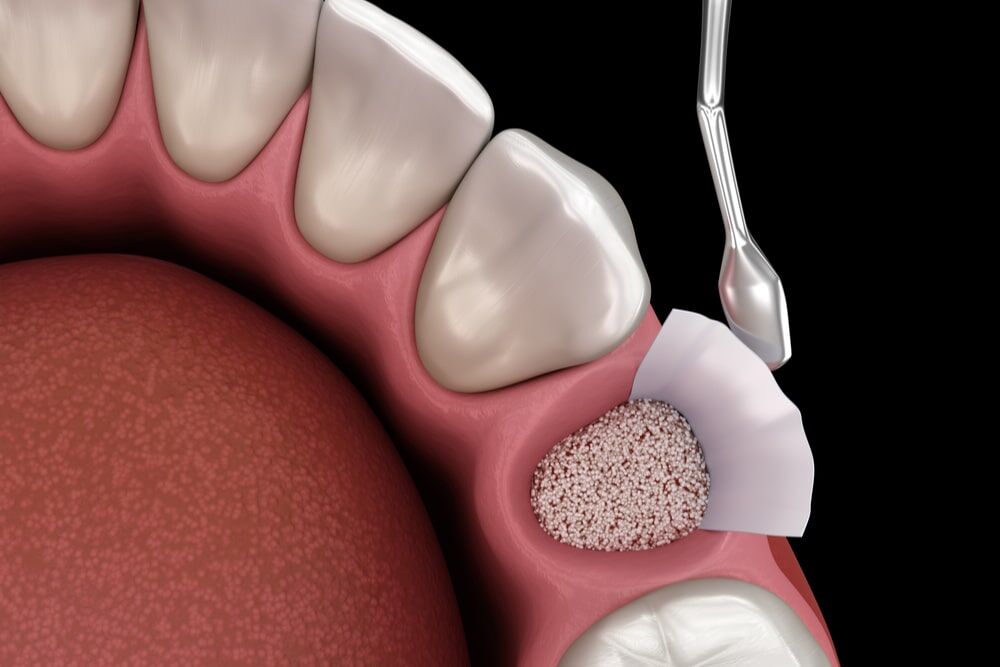

3. Кюретаж десны и альвеолярной кости

Кюретаж — это процедура очистки воспаленных тканей десны и кости вокруг зуба. Чаще всего она проводится при заболеваниях пародонта, когда бактерии проникают под десну и вызывают воспаление. При глубоких поражениях десны проводят глубокий кюретаж, позволяющий очистить патологические ткани и остановить прогрессирование заболевания. Кюретаж позволяет избежать распространения воспаления на корень зуба и сохранить его.